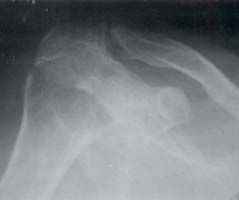

Pueden observarse erosiones, estrechamiento del espacio articular, o subluxación superior. El estrechamiento entre el acromion y la cabeza humeral es el resultado de lesión del manguito de los rotadores. Los cambios erosivos pueden ocurrir en el extremo distal de la clavícula, en el aspecto lateral superior de la cabeza humeral adyacente a la tuberosidad mayor y en la unión del ligamento coracoclavicular con la clavícula16. (Figuras 3-6).

Figura 3. Hombro. Disminución del espacio

articular, deformidad de la cabeza, presencia

de quistes subcondrales

Figura 4. Hombro. Disminución del

espacio articular. Esclerosis subcondral

y erosiones subcondrales.

Figura 5. Subluxación de la cabeza humeral.

Compromiso de la articulación acromioclavicular.

Figura 6. Hombro. Disminución marcada

del espacio articular de manera concéntrica,

esclerosis y quistes subcondrales.